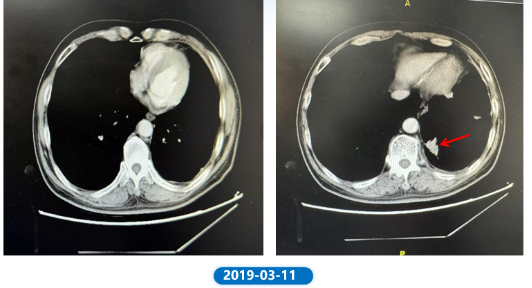

• 2018.12.06 给予培美曲塞0.9g +贝伐珠单抗0.5g治疗2周期后因鼻衄停用贝伐珠单抗。2019.01.30给予培美曲塞0.9g治疗1周期。2019.03.11复查CT,左下肺结节(1.68*2.3cm)较前增大。

肺“长”实“例” :从真实世界病例看EGFR ex20ins NSCLC患者综合治疗模式下的长生存漫漫路1230.png